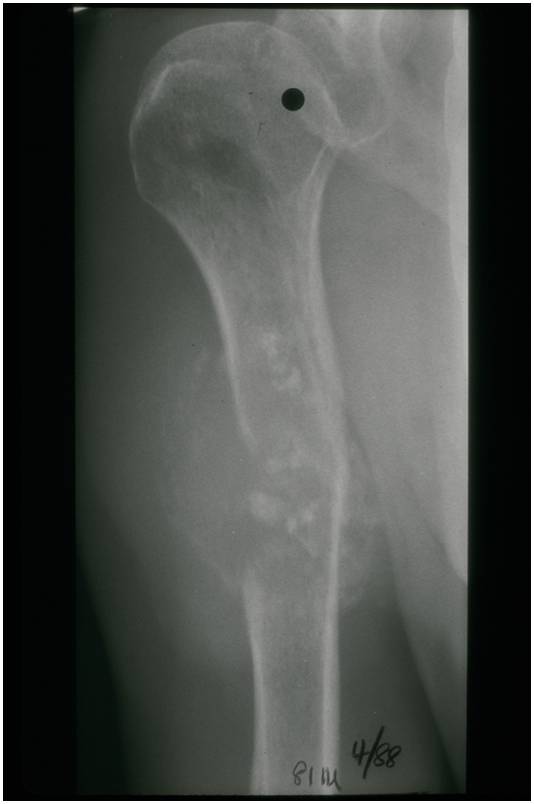

Radiographic Presentation

Radiology emulates pathology: Biphasic Tumor

- One region low grade chondrosarcoma

- Second more aggressive area with bone destruction, lysis of calcification, soft tissue mass

- Cortical permeation and a soft tissue mass in 70% of cases

Ill-defined, lytic intraosseous lesion

- Or extraosseous soft tissue mass

- Devoid of calcifications in continuity with lesions having the features of a cartilaginous tumor

Characteristically abrupt transition between chondroid tumor and dedifferentiated, lytic component

Bone may be expanded and adjacent cortex thickened

(Right Arrow)Aggressive Lytic Area (Dedifferentiated Sarcomatous Component) Cortical Destruction Soft Tissue Mass without Calcification